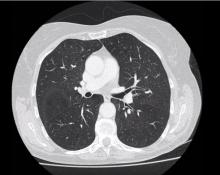

Redo Right Upper Lobe Microlobectomy After Previous Middle Lobectomy [1]

This video shows a redo right upper lobe microlobectomy for a second primary tumor. The authors previously performed a posterior approach middle lobectomy on the patient in 2014. Footage from both operations is shown in this video, so that the differences in approaches can be seen. Interestingly, the fissure was very good in the first operation and this was preserved in the redo operation, despite additional peripheral adhesions. The authors encourage all surgeons to save videos of previous operations. In this case, the 2014 video of the original operation helped the authors prepare for the redo operation.